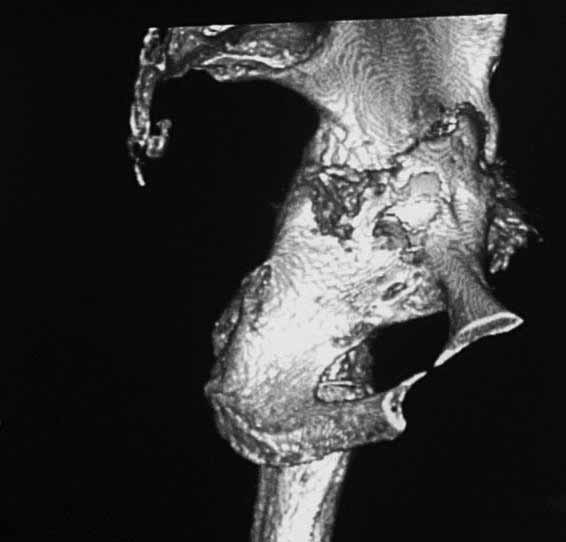

Уважаемые коллеги. Хотелось бы услышать мнения и советы по представляемому случаю. Пациентка 45 лет. Бесцементное эндопротезирование левого тазобедренного сустава 6 лет назад (впадина RM, Mathys, металл-металл, ножка Зульцеровская). За 10 лет до протезирования – коррегирующая остеотомия бедренной кости, которая не срослась в течение года до удаления пластины, а затем срослась в течение 3 месяцев иммобилизации в кокситной повязке. После протезирования получилось наблюдать пациентку почти постоянно, поскольку через 2 года синтезировал ей лодыжки на оперированной стороне, затем, через несколько месяцев удалил фиксаторы, а в 2009г. резецировал мениск на противоположной стороне. Боли все эти годы не беспокоили. Пациентка чуть выше среднего роста, вес тела нормальный. Физические нагрузки переносила хорошо. Работает на 7 этаже без лифта. Год назад экстирпация матки по поводу лейомиомы больших размеров. Несколько месяцев назад появились боли в области левого тазобедренного сустава. При рентгеновском и КТ исследованиях (июль с.г.) – нестабильность тазового компонента. От предложенной замены протеза пациентка на тот момент, слава богу, отказалась. Через какое то время боли в области левого тазобедренного сустава практически полностью прошли, а около 2 месяцев назад появилось ощущение патологической подвижности таза и боли в паху справа, которые через некоторое время уменьшились, а потом снова усилились после значительных физических нагрузок (много ходила по песку на пляже, носила тяжести). Ежедневно принимала диклофенак. На рентгенограммах – переломы правой лонной кости. Сейчас госпитализирована из-за болей в паху справа. Боли слева не беспокоят. На фоне снижения нагрузок в стационаре боли значимо уменьшились. Способна ходить без средств дополнительной опоры.В анализах крови чуть повышены трансаминазы и гамма-ГТ, моча без особенностей.

Вопросы: -правильно ли я расцениваю переломы как стрессовые на фоне неполноценного таза (pelvic insufficiency stress fractures)? -Можно ли так же расценить ситуацию на стороне протеза и, соответственно, не торопиться с ревизией, рассчитывая на вторичную стабилизацию? Уж больно не хочется менять ножку. -Если думать о ревизии, то когда? На представленных снимках тазобедренный сустав до и сразу после операции, затем 2 снимка 2009г., когда ничего не беспокоило, затем КТ 2-х месячной давности и вчерашние рентгенограммы обоих тазобедренных суставов.

При сравнении рентгенограмм можно увидеть насколько чашка переместилась от места своего первичного расположения. От опрокидывания ее удерживают конструкционные элементы "рожки". Без них ситуация, возможно, уже была бы катастрофической (чашка в тазу). Думаю надежды на вторичную интеграцию, могут быть обмануты и ревизии не избежать.

Если говорить о ревизии, то просто не будет и вероятность установки реконструктивного кольца достаточно высока, однако можно попробовать установить бесцементную высокопористую (для вторичной стабилизации врастанием) чашку с винтами , а по ходу операции решить вопрос о необходимости стабилизации таза пластиной.